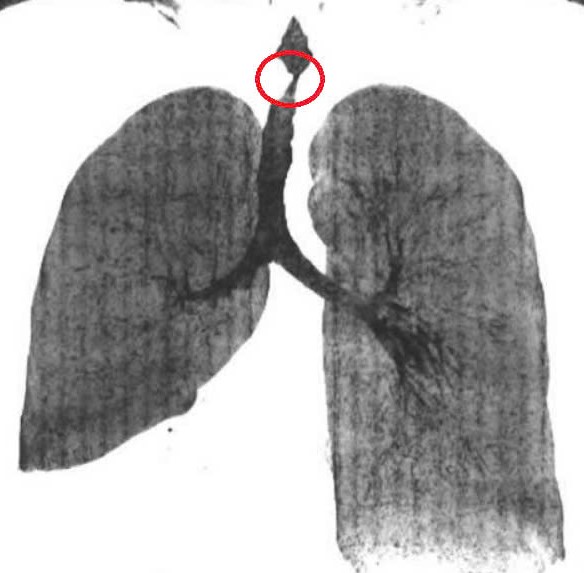

Chị Mai,36 tuổi,mắc bệnh lao phổi 4 năm trước,uống thuốc 6 tháng thì khỏi. Ba năm sau,chị bị hẹp khí quản do di chứng lao phổi. Sau điều trị bệnh lao,mô sẹo xơ phát triển vào trong lòng khí quản gây hẹp đường thở tăng dần. Đoạn hẹp dài 3 cm,chỗ hẹp nhất là 3x8 mm như sợi chỉ,trong khi đường kính khí quản người lớn khoảng 12 mm.

Khí quản hẹp khít một đoạn dài khiến bệnh nhân khó thở,mệt mỏi kéo dài. Ảnh: Bệnh viện Tâm Anh